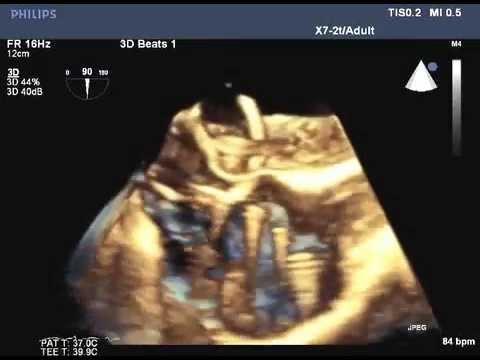

Video 7.3

Video 7.3 Real-time three-dimensional (3D) imaging is used more frequently to help guide transseptal catheter placement. This is an example of real-time 3D imaging showing the transseptal catheter in the left atrium.